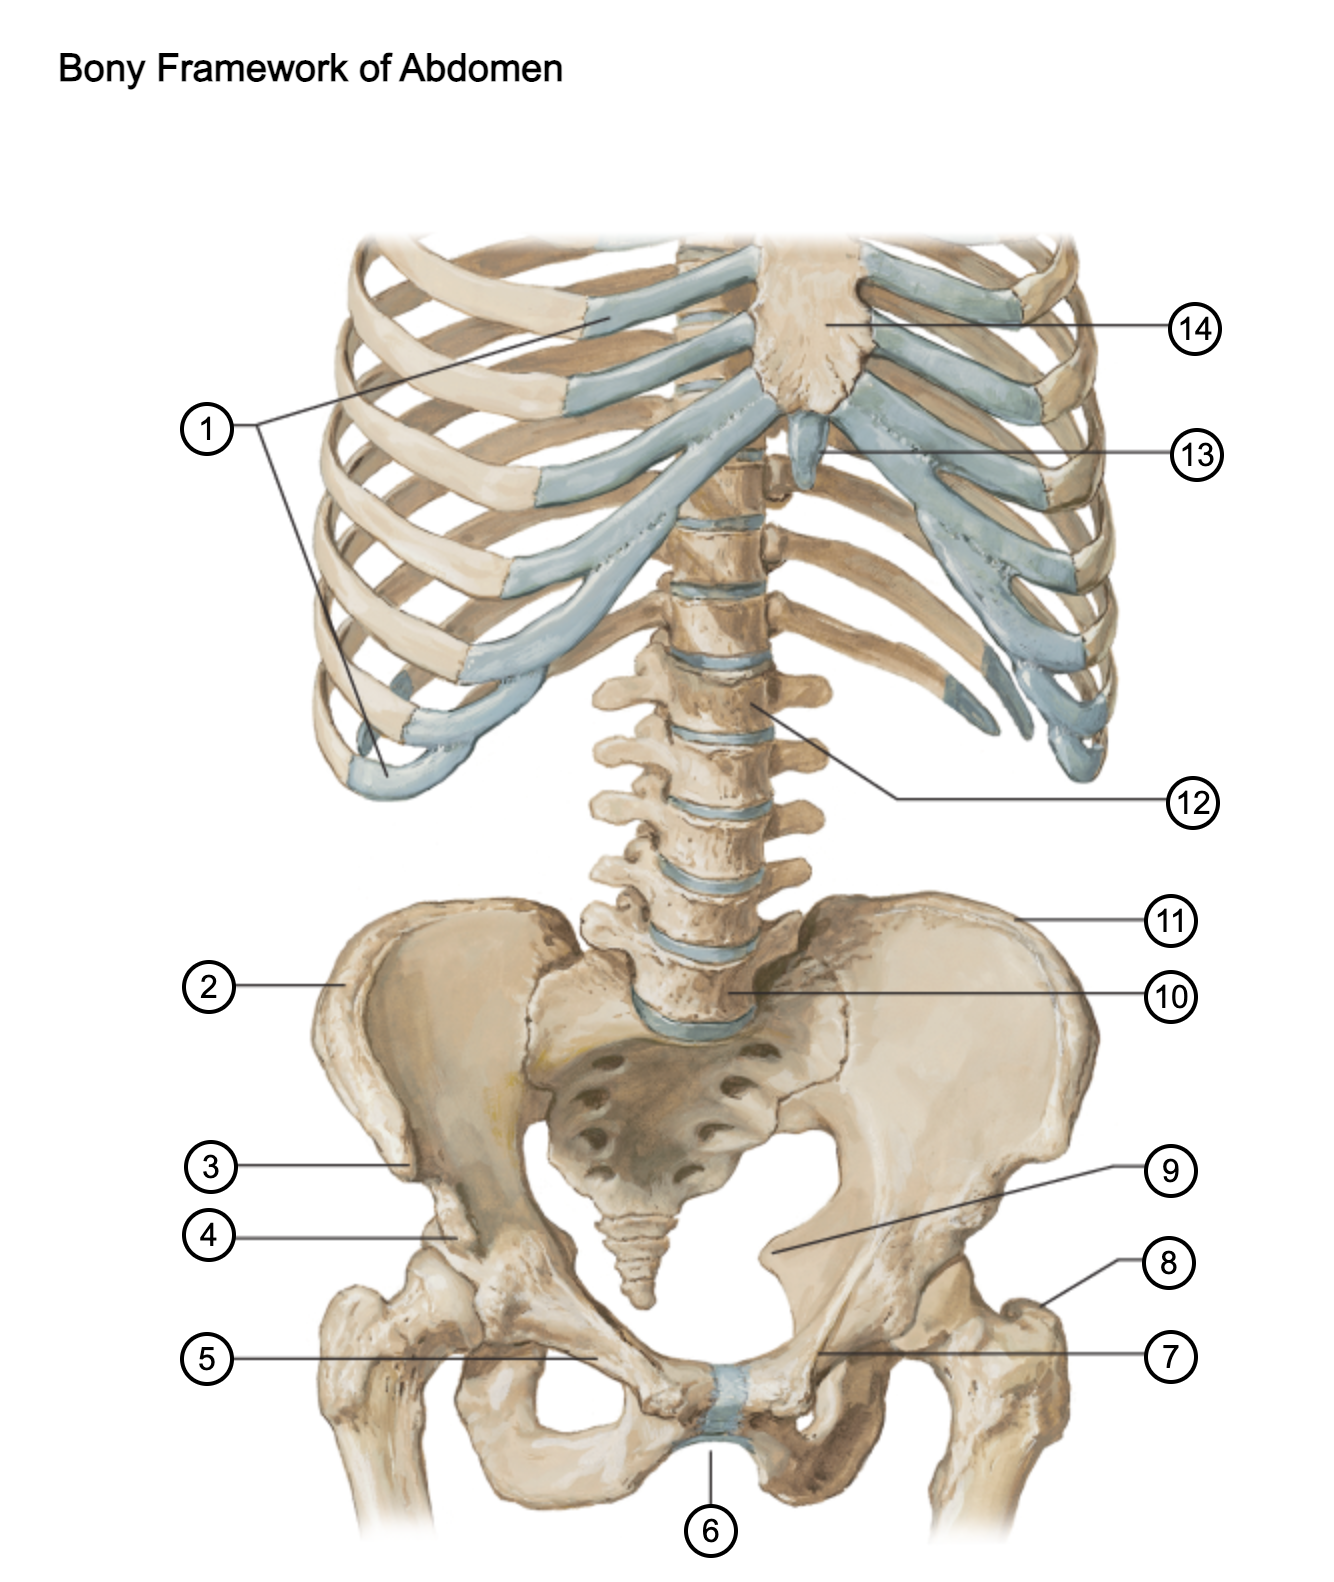

1

costal cartilages

2

iliac crest

3

anterior superior iliac spine

4

anterior inferior iliac spine

5

superior pubic ramus

6

pubic arch

7

pecten pubis

8

greater trochanter

9

ischial spine

10

L5 vertebra

11

iliac crest

12

L1 vertebra

13

xiphoid process

14

body of sternum